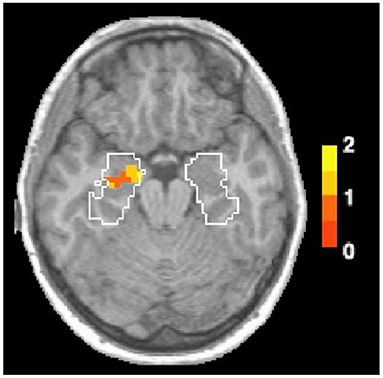

Forskere kan bruge hjernescanninger kaldet functional magnetic resonance imaging (fMRI) til at måle hjerneaktivitet, mens folk udfører mentale opgaver. Fordi fMRI ser på, hvordan hjernen fungerer [4], kan det hjælpe forskere med at se, hvilke dele af hjernen der er mere (eller mindre) involveret, når folk husker fortiden som reaktion på lugte eller billeder. Forårsager lugt-relaterede minder en anden hjerneaktivering end billed-relaterede minder? Ja! fMRI-data viser, at de områder i hjernen, der behandler følelser, er mere aktive, når folk har lugtrelaterede minder end minder fremkaldt af billeder (figur 1) [5].

Mange års forskning har hjulpet os til at forstå, at de følelsesmæssige områder i hjernen – de samme områder, der aktiveres af lugte – omfatter amygdala og hippocampus som er placeret i tindingelapper (figur 2). Tindingelapperne befinder sig under kraniet i nærheden af venstre og højre tinding. Hippocampus er et søhesteformet hjerneområde, som er involveret i associativ læring, som er læring, der opstår, når man forbinder to separate begivenheder. Lugthukommelse er afhængig af associativ læring, fordi vi forbinder den lugt, vi lugter, med det eller de tidspunkter i vores liv, hvor vi tidligere har lugtet den. Som du kan se i figur 2, ligger amygdala og hippocampus meget tæt på hinanden, hvilket gør det nemt for os at lære og huske følelsesmæssige minder.